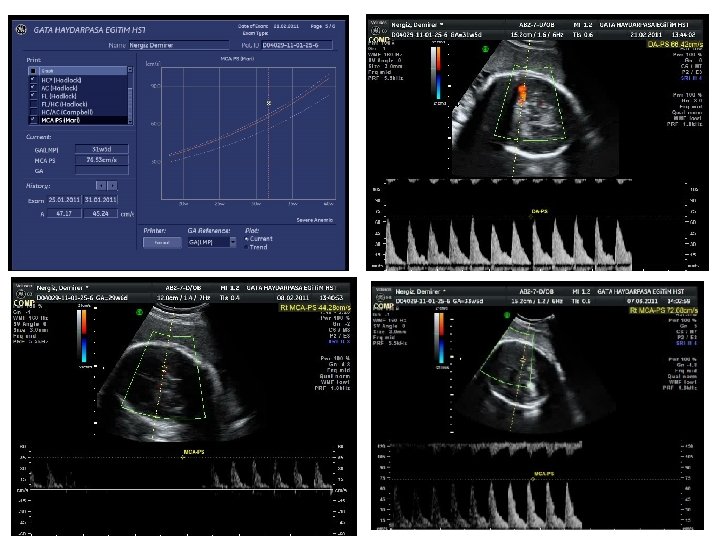

TANI YÖNTEMLERİ • İlk gebelikte sensitizasyon hafif seyreder. • İlk sensitize gebelikte: – Antikor titre takibi anlamlı – Takip aynı ve güvenilir bir laboratuvarla yapılmalı – 24. gebelik haftasına kadar ayda bir, bundan sonra 2 -4 haftada bir titre bakılmalı • Sensitizasyondan sonraki gebeliklerde: – Antikor titrasyonu anemiyi güvenli şekilde öngörmez – 18. gebelik haftasından itibaren MCA-PSV takibi gerekir.

Tanı Yöntemleri-Ultrasound-MCA Doppler – Şiddetli anemik fetusta periferal dokulara oksijen iletimini artırmak için kardiak output artar. – Kan viskozitesi azalır. Doppler ultrasonla fetal MCA pik sistolic hız (PSH) değerlendirmesi fetal aneminin öngörüsünde kullanılmaktadır. Gebelik haftasına göre 1. 5 MOM’dan (multiples of the median) daha yüksek PSH değerleri, % 88 sensitivite ve % 89 negatif prediktif değerle orta derecede-ağır fetal anemiyi öngörür. Mari G. Noninvasive diagnosis by Doppler ultrasonography of fetal anemia due to maternal red-cell alloimmunization. N Engl J Med. 2000; 342: 9 -14

• MCA ölçümleri 18. gebelik haftasından itibaren güvenilir olarak yapılabilir. • Ölçümler, trende göre 1 -2 hafta ara ile tekrarlanmalı. • Dikkat!!! – MCA’in distalinden yapılan ölçümlerde yanıltıcı olarak daha düşük MCA pik akım hızı elde edilir. – Fetal hareket sırasında fetal kalp hızı arttığından pik akım hızı daha düşük çıkar (özellikle geç üçüncü trimesterde) – Antenatal steroid uygulamasını takiben MCA pik akım hızında geçici azalma olur (bu etki son dozdan itibaren 24 -48 saat devam eder).

İntrauterin Transfüzyon • Amaçlanan nihai fetal hematokrit % 40 -50 dır. • İlk IUT’dan sonra, takibeden işlemler fetal eritropoez suprese oluncaya kadar ampirik olarak 14 gün aralarla planlanabilir. • Bu genellikle üçüncü tranfüzyonda oluşur. • Daha sonra hangi aralıklarla işlemin tekrarlanacağı her bir fetustaki hemtokrit değerinin düşmesine bağlıdır (genellikle 3 -4 haftalık intervallerle) • MCA da PSV ölçümünün ikinci IUT’nun zamanını belirlemede kullanılabileceği gösterilmiştir. – Bazı çalışmalarda ikinci tranfüzyon için MCA’da 1. 32 Mo. M’u eşik değer olarak önerilmiştir; günümüzde?

İntrauterin Transfüzyon • İkinci işlemden sonra , MCA Doppler fetal anemi öngörüsündeki değerini kaybeder (fetustaki eritrosit kitlesinin çoğunu transfüze edilen erişkin eritrositleri oluşturduğundan ve buna bağlı olarak değişen akım özellikleri –rheology- nedeniyle) • 35. gebelik haftasından sonra IUT yapılmaz ve son transfüzyondan 3 hafta sonraya doğum planlanır. • Retrospektif bir çalışmada, doğumdan önce 10 gün süre ile oral fenobarbital 3 X 30 mg uygulamasının, hiperbilirubinemi nedeniyle neonatal exchange transfüzyon gerekliliğini % 75 azalttığı gösterilmiştir (Fetal KC matürasyonu). Trevett TN Jr, et al. Am J Obstet Gynecol. 2005; 192(2): 478